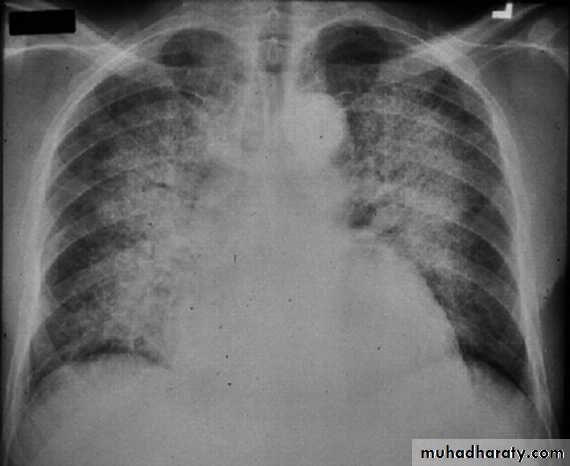

BNP brain natriuretic pepetideChest X-ray in Heart Failure

CardiomegalyCephalization of the pulmonary vessels

Kerley B-lines

Pleural effusions

Cardiomegaly Pulmonary vessel congestion

Pulmonary Edema due to Heart Failure

Kerley B lines